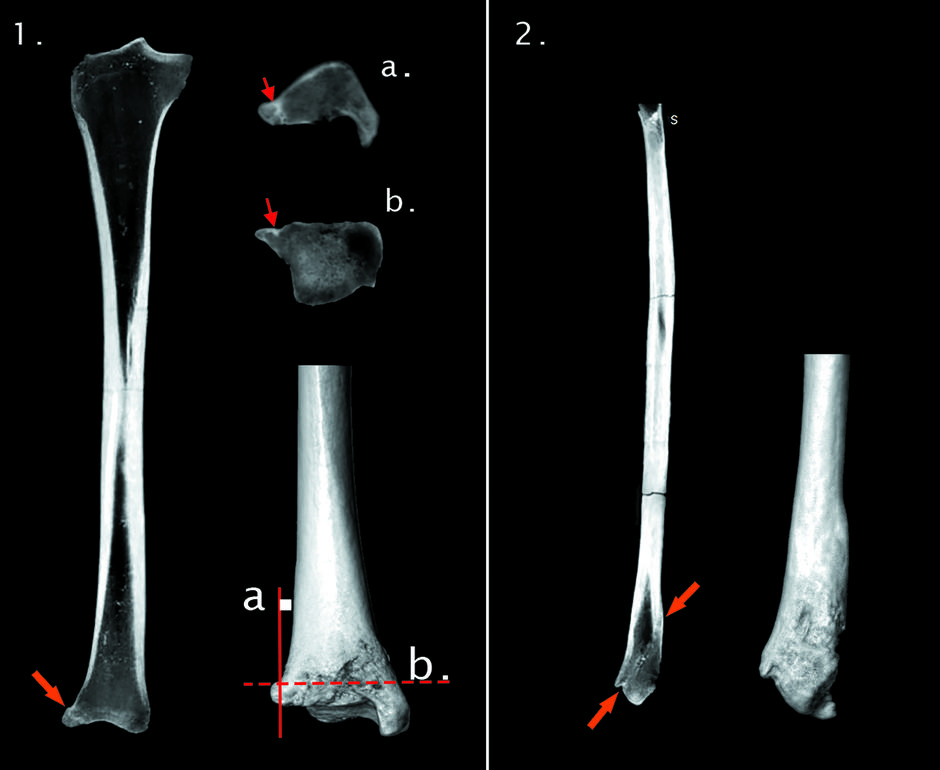

• Tajna hoda: Znanstvenici su uočili staru, zaraslu ozljedu desnog skočnog zgloba, zbog koje je grofica vjerojatno primjetno šepala.